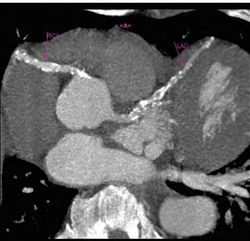

| − | + | [[Image:IBS.jpg|250px|thumb|right|На компьютерной томографии обширный кальциноз коронарных артерии у 48-летнего культуриста, злоупотреблебляющего ААС]] | |

Известно, что употребление анаболиков связано с заболеваниями сердечно-сосудистой системы. Вероятно, это взаимосвязано с их влиянием на холестерин. Помимо этого, злоупотребление препаратами этой группы может вызывать гипертрофию желудочков сердца. Однако стоит заметить, что к этому приводит и силовой тренинг.